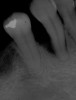

Fig 25. Post-treatment, healthy bone and ideal implant placement were observed radiographically.

Figure 25